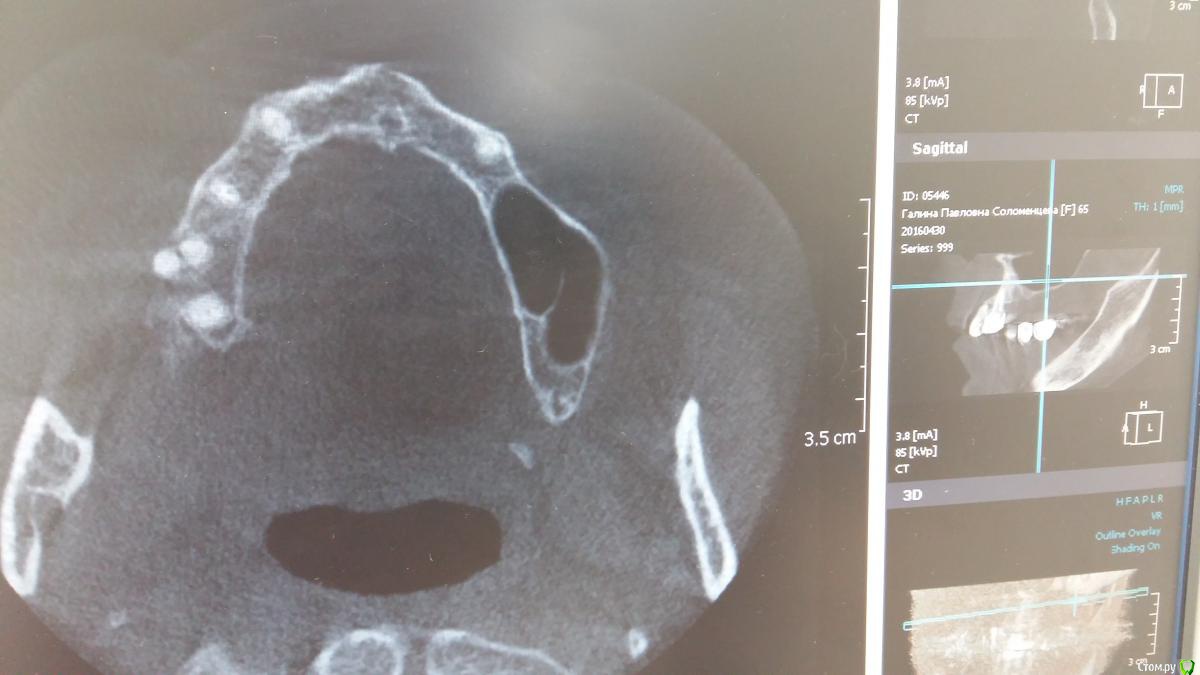

Zubnik7 Опубликовано 30 сентября, 2016 Автор Поделиться Опубликовано 30 сентября, 2016 Перегородка не полная,сейчас выложу новые срезы,более информативные Ссылка на комментарий

Zubnik7 Опубликовано 30 сентября, 2016 Автор Поделиться Опубликовано 30 сентября, 2016 Новые срезы Ссылка на комментарий

voff Опубликовано 14 февраля, 2017 Поделиться Опубликовано 14 февраля, 2017 Прикидывал разные варианты, но в любом случае имплант попадает в перегородку или близко к ней. http://s06.radikal.ru/i179/1702/49/acc48d8867ca.jpg Ссылка на комментарий